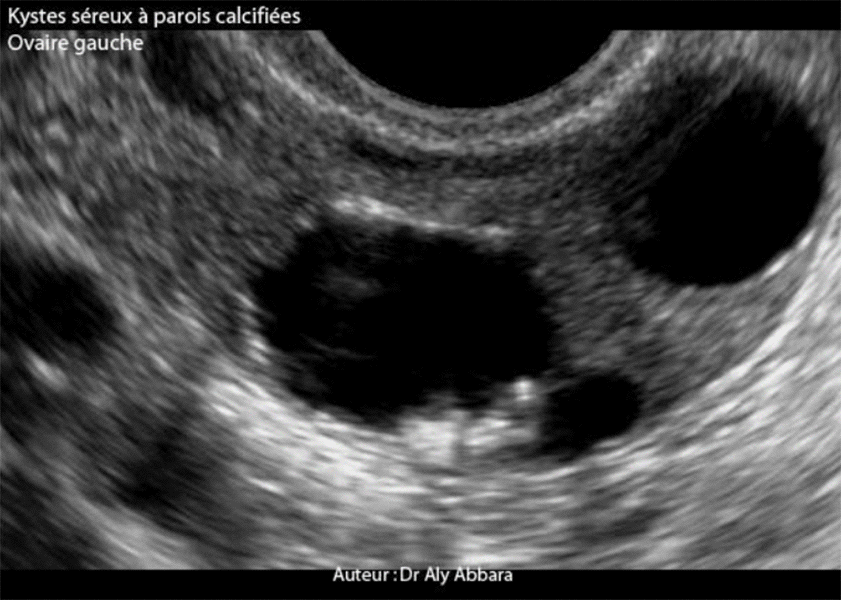

Ovaire gauche porteur de deux petits kystes séreux

L'ovaire gauche : Petits kystes séreux bénins de (18 x 16 x 15 mm et 16 x 15 x 15 mm) à

parois fibreuses et calcifiées

Echographie : les parois kystiques sont à certains endroits granuleuses et hyper-échogènes